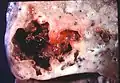

Lung abscess is a type of liquefactive necrosis of the lung tissue and formation of cavities (more than 2 cm)[1] containing necrotic debris or fluid caused by microbial infection.

- Pathology image of a lung abscess.